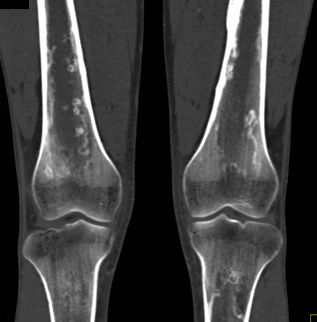

The best dx in this case is

lymphoma

fibrous dysplasia

sickle cell disease with bone infarcts

bone metastases